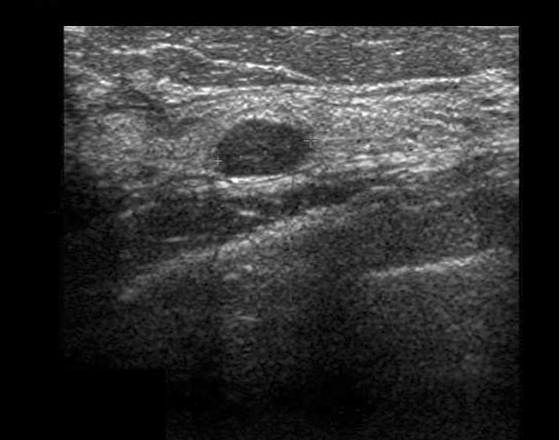

Kyste à contenu épais | Iconographie précédente | Retour cours | Index iconographique | Iconographie suivante |